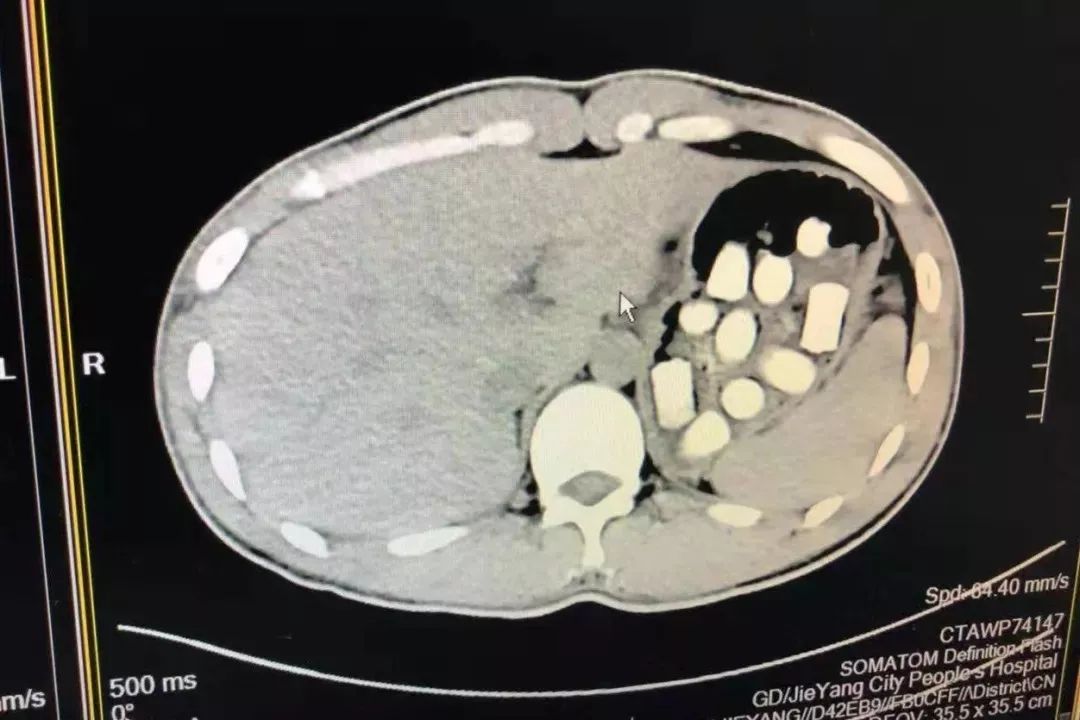

胃部CT图像“消消乐”,满藏*品毒**

随后,民警将嫌疑人带往市某医院做CT检查,医生发现嫌疑人胃部分布着密密麻麻胶囊状异物,约有50块阴影!考虑到犯罪嫌疑人年轻且身体状况良好,医生建议由其自行排放出体外,以免胶囊状异物破裂。随后警方将犯罪嫌疑人带回办案区进行审查看管并“排毒”。审讯期间,郑某不时进行排便。9月4日至6日二天内,民警在郑某排出来的粪便中,共提取到55粒胶囊状(高22mm,直径15mm,净重量274.63克)的疑似*品毒**物体,检鉴定结果为*品毒***洛因海**!

9月6日下午,郑某在做入所前体检查时,仍发现体内有十多粒胶囊状*品毒**。随后二天,郑某再次排出二粒*品毒**后,出现短暂昏迷,考虑到嫌疑人生命安全,经再送市级三甲医院检查,郑某的胃肠中还有10多粒胶囊状*品毒**,其中一粒在胃里滞留,或可能已经破损,*品毒**泄漏到体内,致身体中毒出现昏迷,随时危及生命!